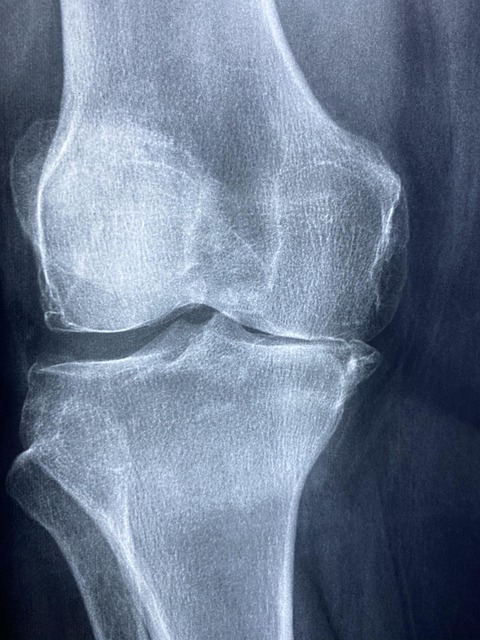

50대 여성에게 류머티즘은 흔하지만 쉽게 지나칠 수 있는 질환입니다. 손가락, 무릎, 손목 등의 관절에 통증이나 뻣뻣함이 반복되며, 아침에 일어날 때 관절이 잘 움직이지 않는 증상을 경험하게 됩니다. 이는 단순한 관절염이 아니라 면역계의 이상 반응으로 인해 발생하는 류머티즘일 수 있습니다. 초기에는 약간의 통증과 피로감으로 시작되지만, 시간이 지날수록 관절 손상이 진행되어 일상생활이 어렵게 됩니다. 특히 여성은 남성보다 류머티즘 발생률이 2~3배 높고, 50대 이후 폐경과 함께 면역 기능이 불안정해져 발병 위험이 더 커집니다. 예방을 위해서는 정기적인 건강검진과 함께 다음과 같은 생활습관이 필요합니다. 첫째, 균형 잡힌 식사를 통해 면역력을 강화해야 하며, 오메가-3 지방산이 풍부한 생선, 항산화 효과가 높은 채소와 과일을 충분히 섭취하는 것이 좋습니다. 둘째, 관절 부담을 줄이기 위한 스트레칭과 유산소 운동도 매우 중요합니다. 특히 수영이나 요가는 무릎 관절에 무리를 주지 않으면서 근육을 단련할 수 있어 효과적입니다. 또한 가족력이나 이전에 관절 질환을 겪은 이력이 있다면, 류머티즘 내과 전문의의 진단을 조기에 받아보는 것이 좋습니다. 자가진단 체크리스트나 병원에서 시행하는 혈액검사(CRP, 류머티즘 인자 등)를 통해 빠르게 이상 유무를 확인할 수 있습니다.